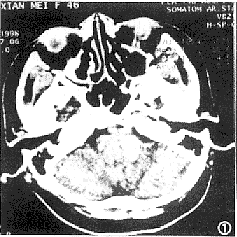

CT扫描: 延髓左侧一1.4cm×2.0cm大小高密度灶,CT值约80HU,境界清楚,延髓轻度受压(图1)。

图1 CT平扫:延髓左侧高密度病灶,CT值80HU,边界清楚 图2、3 MRI横断面T1WI高信号、T2WI低信号